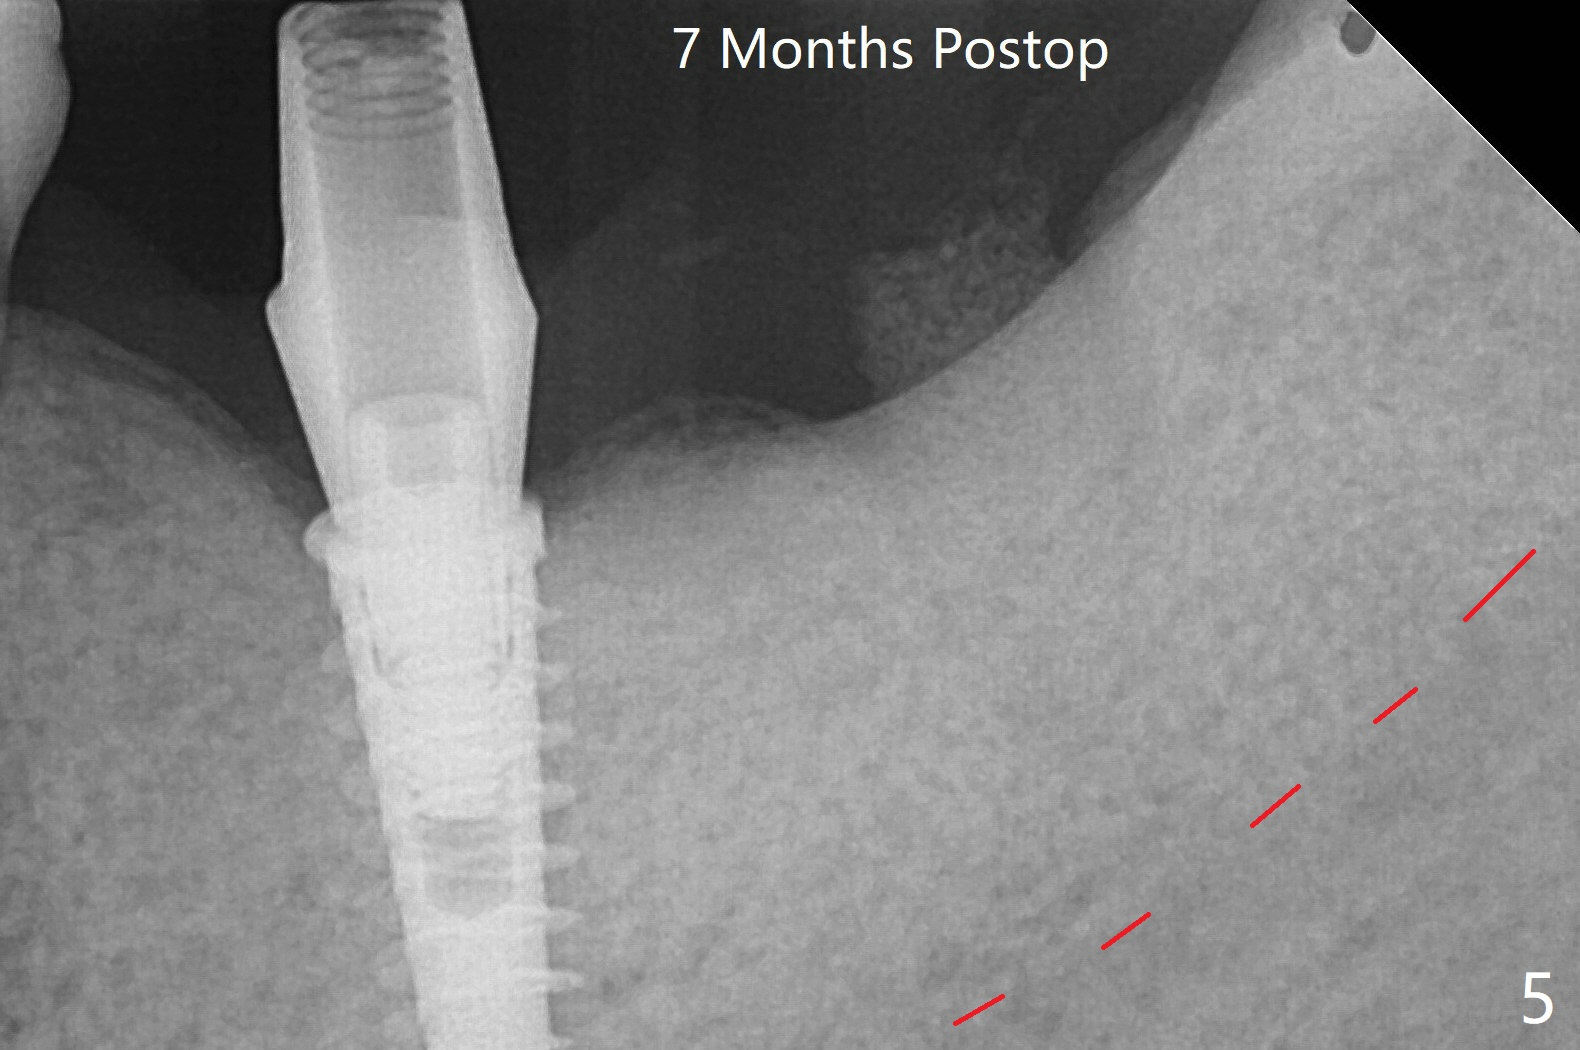

Following placement of a 4.5x11 mm implant at #19 (14 months post guide fabrication), a fixture anchor pin is placed. With stable guide, it is much easier to finish osteotomy and implant placement at #18 (Fig.1). Since the patient is nervous and sensitive to drilling, a shorter implant is placed (7 mm instead of 9 mm vs. 8.5 mm drill). The stability is unaffected because of the dense bone. After use of 5.5 mm profile drill, healing abutments (5.5x3 and 5.5x4 mm) are placed without interference. There is crestal bone loss in 3 months (Fig.2, as compared to Fig.1). Since there is more space apical to the pair abutment at #19 than that at #18, incomplete abutment seating is suspected at #19. More X-ray will be taken (Fig.3,4). In fact, it is not necessary. The space differential is also noted with healing abutments in Fig.1. BW cannot tell whether the abutment at #19 is seated or not (Fig.3). When the abutment is changed at #19 with 30 Ncm torque, the space differential remains (Fig.4, as compared Fig.2) and must be normal. The shorter implant at #18 appears not osteointegrate, since the patient feels pain when the abutment is torqued at 15 Ncm. The patient returns for temporary crown contour adjustment 1-2 weeks later. The implant at #18 is removed when the abutment screw is untightened 7 months postop; Cortical bone is placed with 6 month membrane (Fig.5). Three months later, incision will be made with reuse of the guide with fixture pin at #19. If a 4.5x9 mm implant cannot be placed, bury a short and/or narrow implant. Impression will be taken for #19 soon. In fact fixture pin cannot be seated. It appears that cancellous bone reforms, presumably low density. Underdrilling is conducted in diameter. The torque is high, but normal drilling is not carried out. The former implant exfoliated probably due to compression necrosis. The new implant is not completely seated, partially out of fear of being close to the Inferior Alveolar Canal (Fig.6). After cortical plate perforation, allograft is placed (Fig.7 *), followed by buccal flap release (periosteum underscored). In fact the implant does not have enough clearance from the Canal (red dashed line: the superior border of the Canal). The abutment at #19 returns to hold periodontal dressing in place. The implant is buried in the bone except lingual 4 months postop (Fig.8,9).